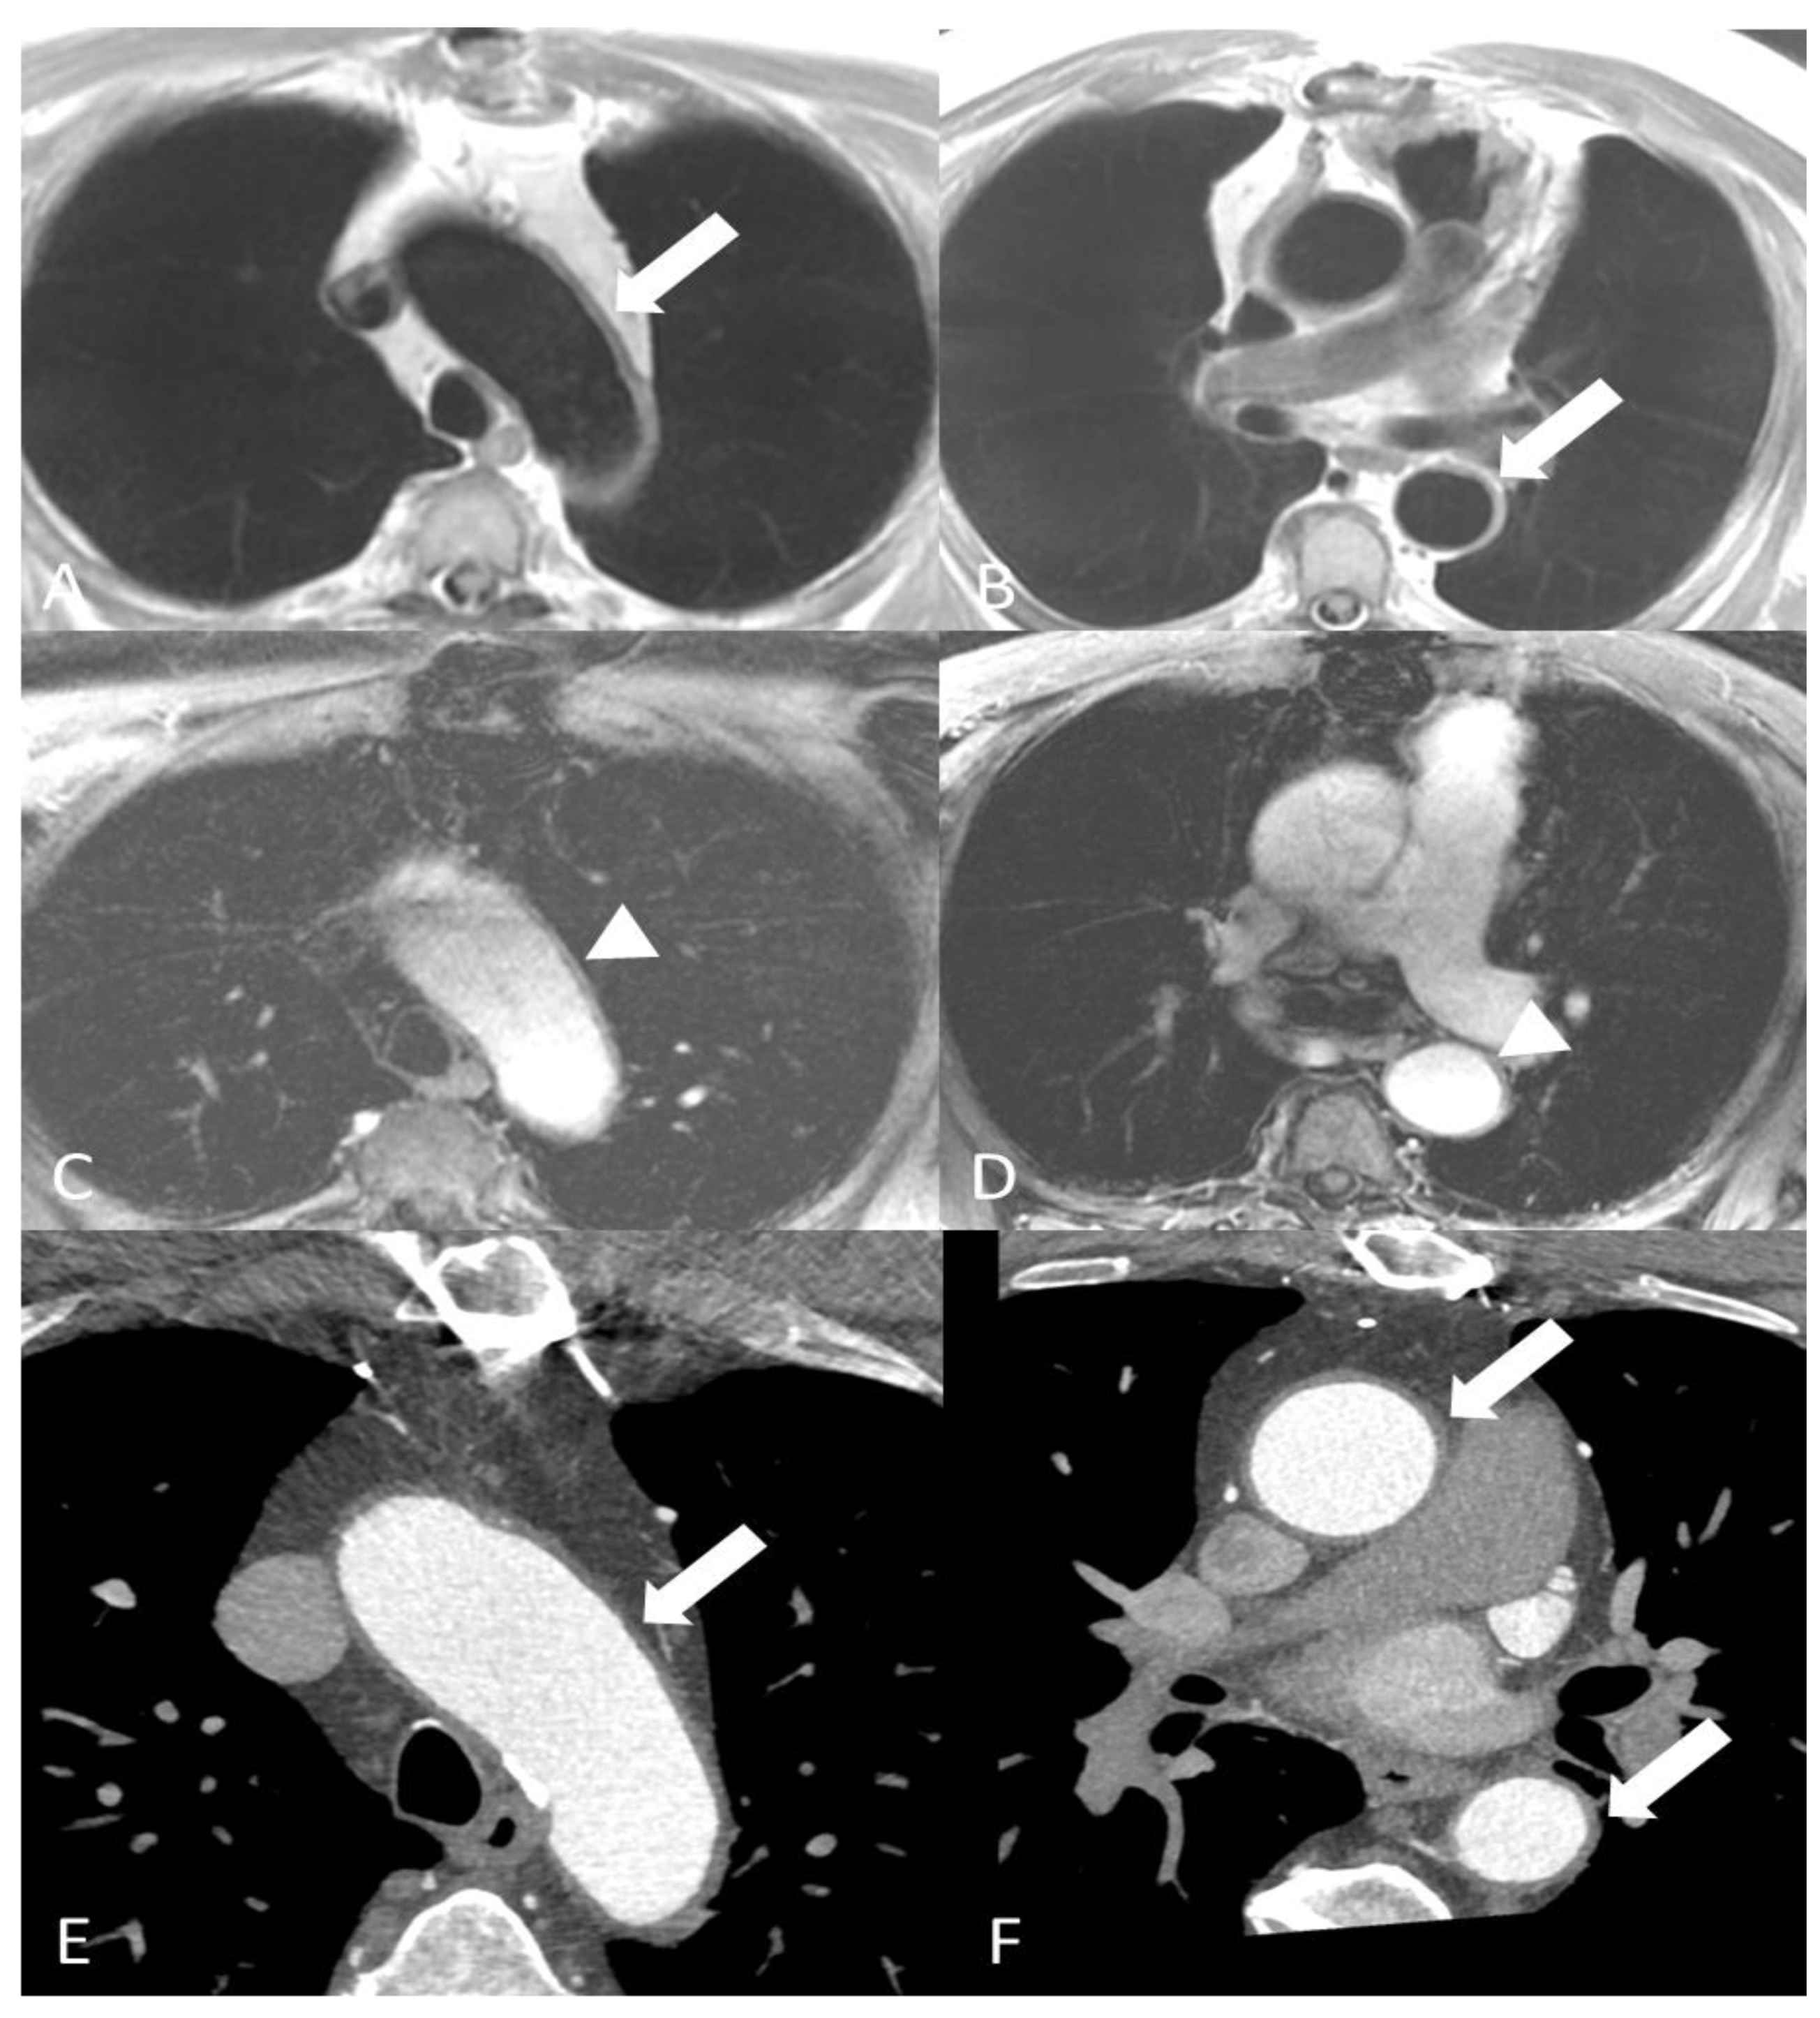

- Papa, M.; Cobelli, F.D.; Baldissera, E.; Dagna, L.; Schiani, E.; Sabbadini, M.; Maschio, A.D. Takayasu Arteritis: Intravascular Contrast Medium for MR Angiography in the Evaluation of Disease Activity. Am. J. Roentgenol. 2012, 198, W279–W284. [Google Scholar] [CrossRef]